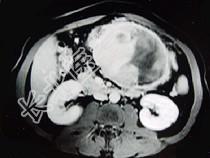

- 单项选择题男,36岁, 腹胀、消化不良、消瘦、中上腹痛,影像检查如下图, 最可能的诊断为 ( )

A、胃间质瘤并肝血管瘤

B、胃淋巴瘤伴原发性肝癌

C、胃间质瘤并原发性肝癌

D、内胚窦瘤肝转移

E、胃间质肉瘤并肝转移